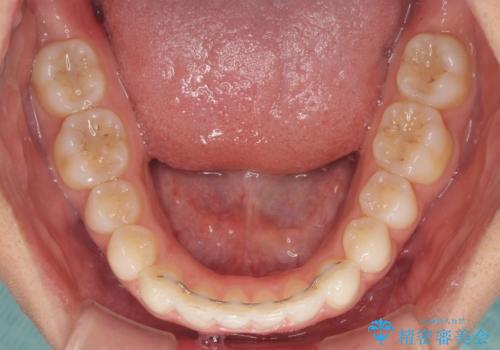

- 深い咬み合わせ(ディープバイト)と前歯のデコボコを気にして来院された患者様です。

インビザラインによる上下歯列の側方拡大と後方移動、IPR(歯と歯の間を削る)にるスペースの獲得により、デコボコとディープバイトを改善することとしました。

後方移動に際し、下顎の親知らずは2本とも抜歯することとしました。

1日22時間の装着時間をしっかり守ってくださったので、予定通り1年で治療を終えることができました。

ディープバイトによる食いしばり癖も解消され、患者様には大変満足していただきました。